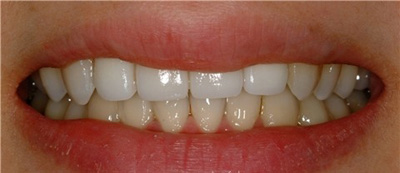

治疗后的照片。

牙齿变得很白喽~看起来很干净的!

现在可以自信的笑啊~哈哈哈